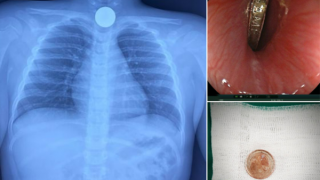

Nội soi gắp đồng xu trong thực quản cháu bé 5 tuổi